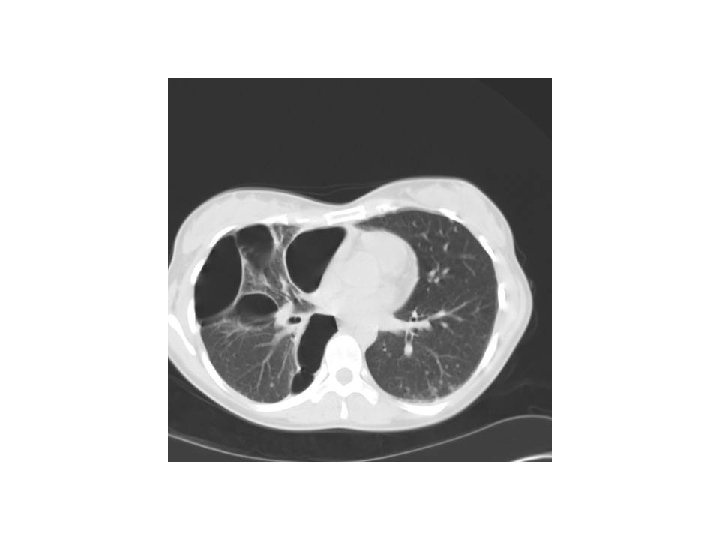

PNO spontanés secondaires Maladies des voies respiratoires Nécrose pulmonaire Pneumopathies chroniques infiltratives diffuses Pneumocystose Fibrose pulmonaire BPCO/emphysème +++ Rupture caverne tuberculeuse Asthme Rupture abcès bactérien Infarctus post embolique Cancer bronchique Mucoviscidose Métastases Nodule rhumatoïde Pneumothorax cataménial (/endométriose pleurale) Histiocytose X Sarcoïdose Lymphangiomyomatose …

Pneumothorax Pleurésie